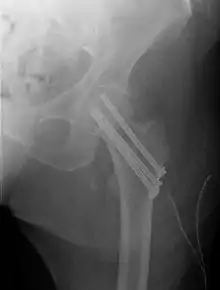

Intracapsular fractures

Fracture treated with cannulated screws

For low-grade fractures (Garden types 1 and 2), standard treatment is fixation of the fracture in situ with screws or a sliding screw/plate device. This treatment can also be offered for displaced fractures after the fracture has been reduced.

Fractures managed by closed reduction can possibly be treated by percutaneously inserted screws.[29]

In elderly patients with displaced or intracapsular fractures many surgeons prefer to undertake a hemiarthroplasty, replacing the broken part of the bone with a metal implant. However, in elderly people who are medically well and still active, a total hip replacement may be indicated. Independently mobile older adults with hip fractures may benefit from a total hip replacement instead of hemiarthroplasty.[30]